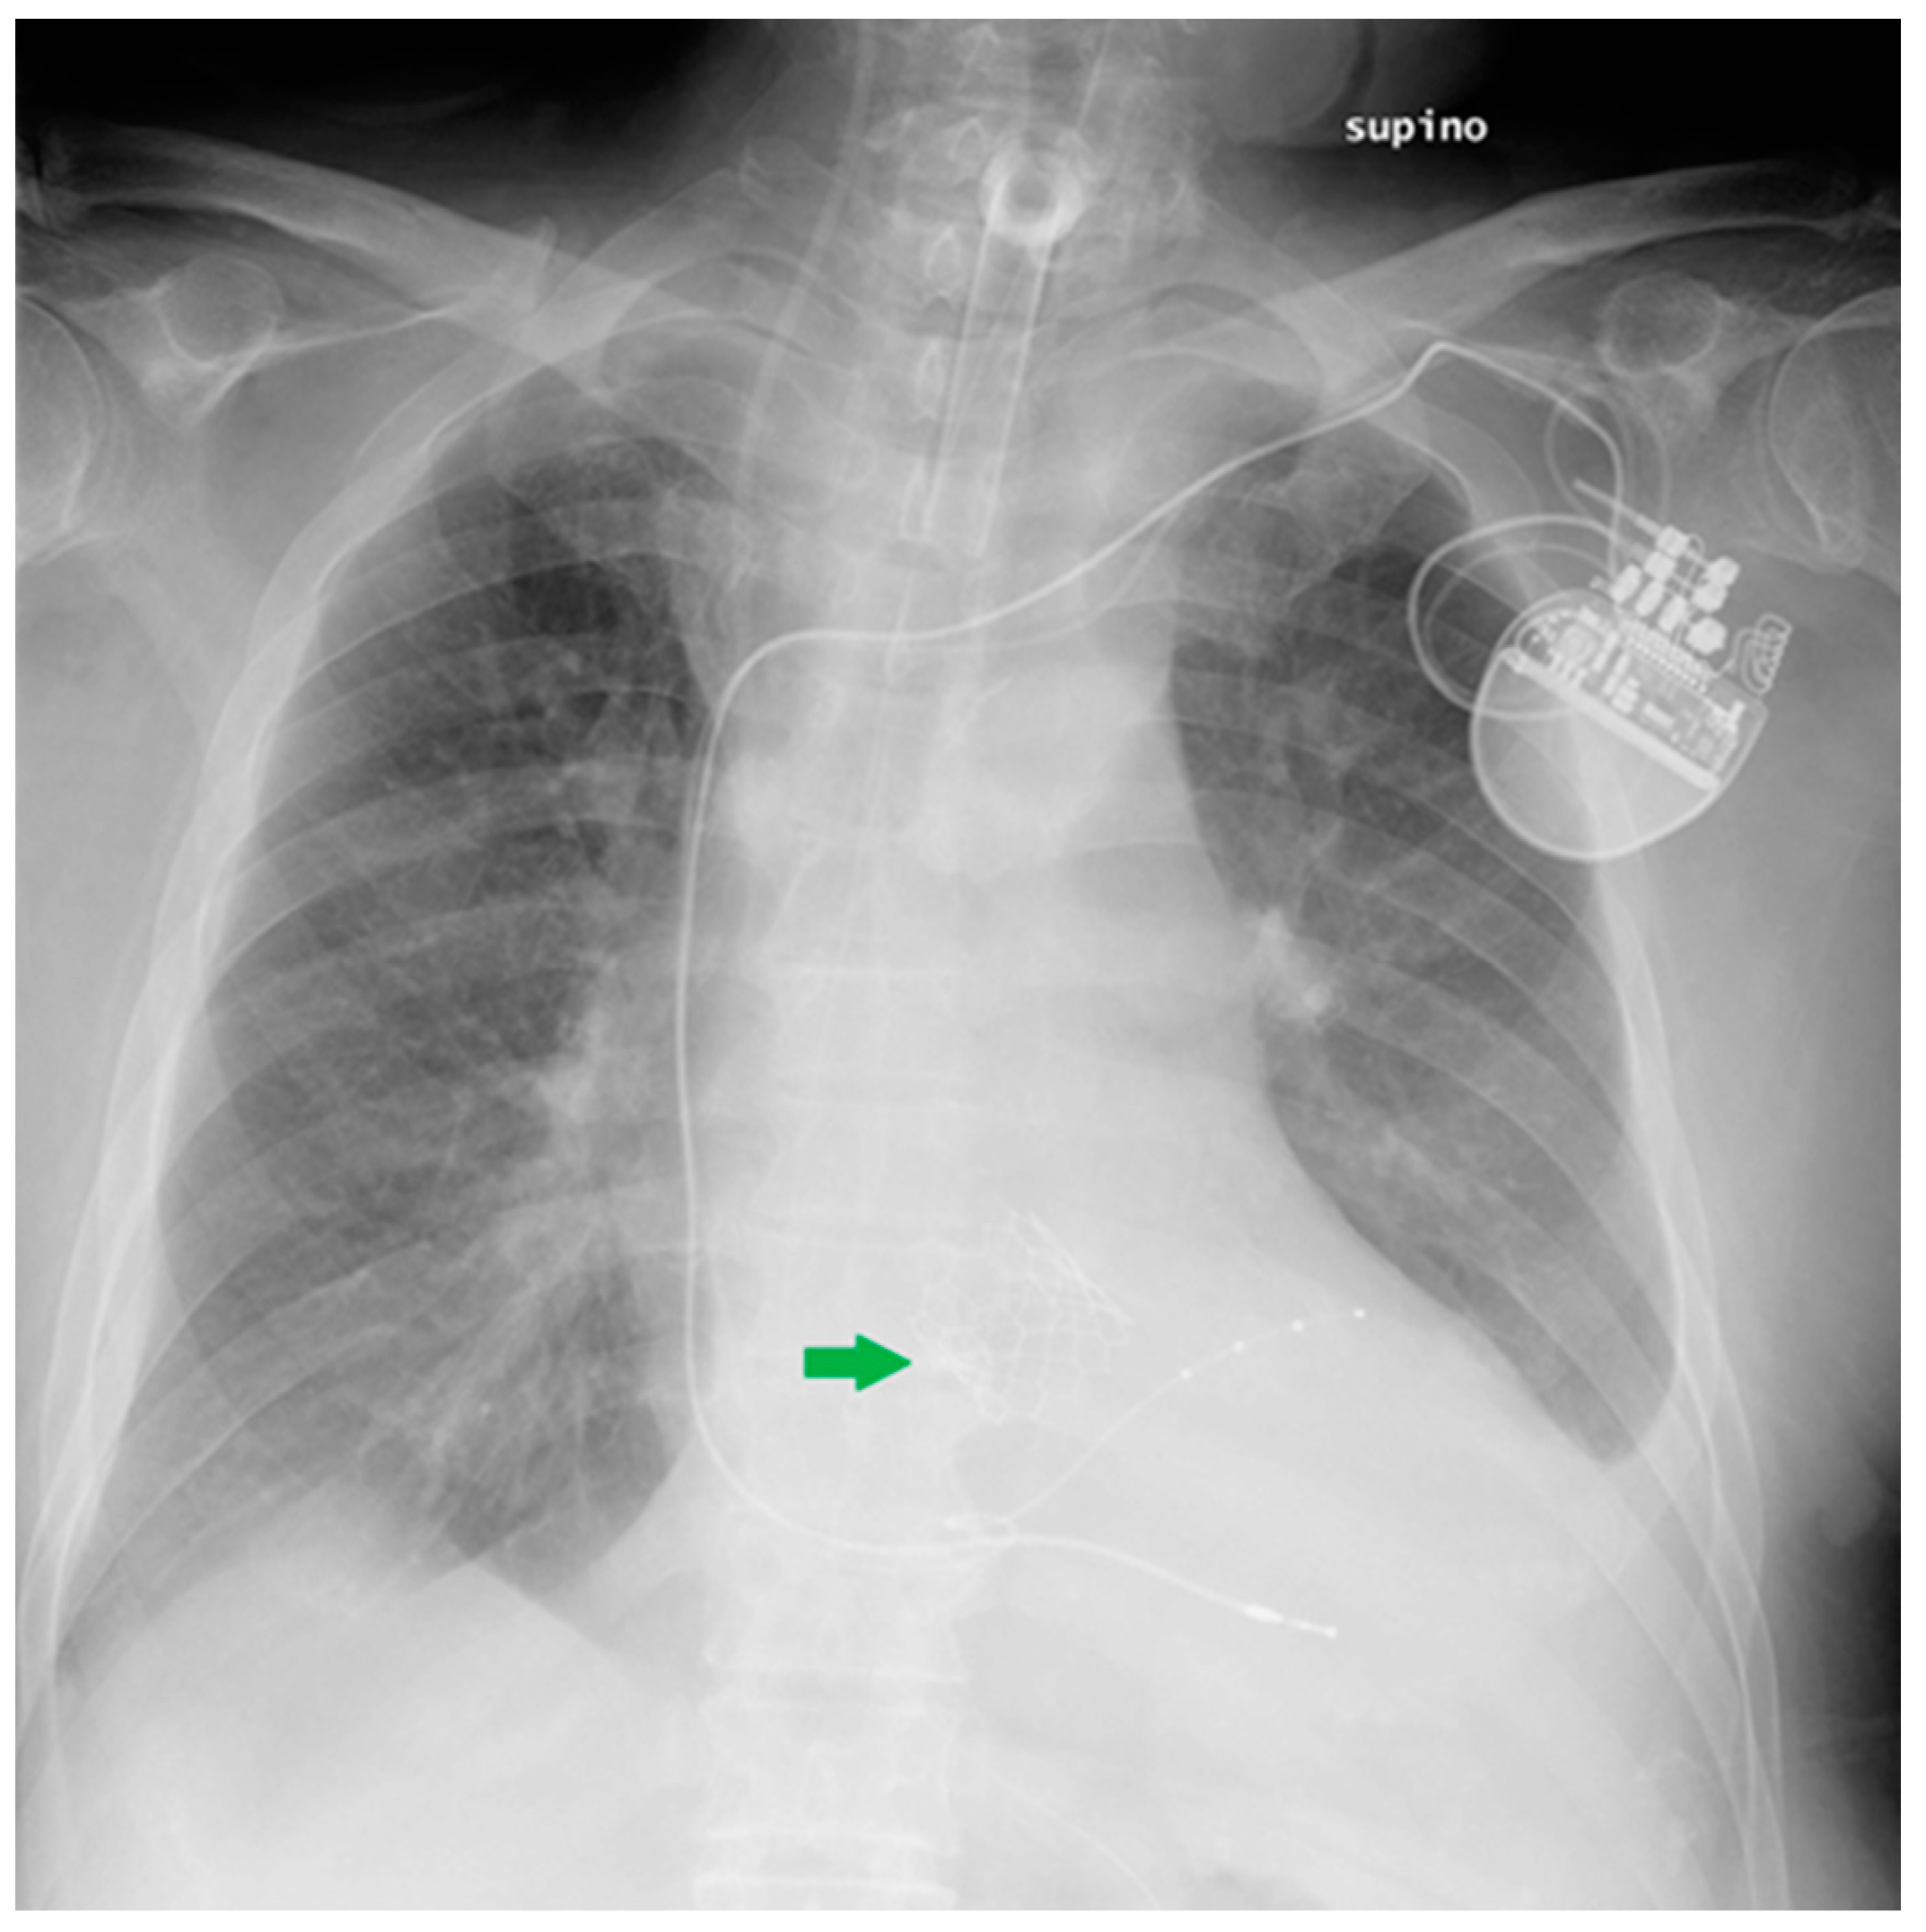

5.1. Loop Recorder

| Loop recorder | Migration (anecdotical) |